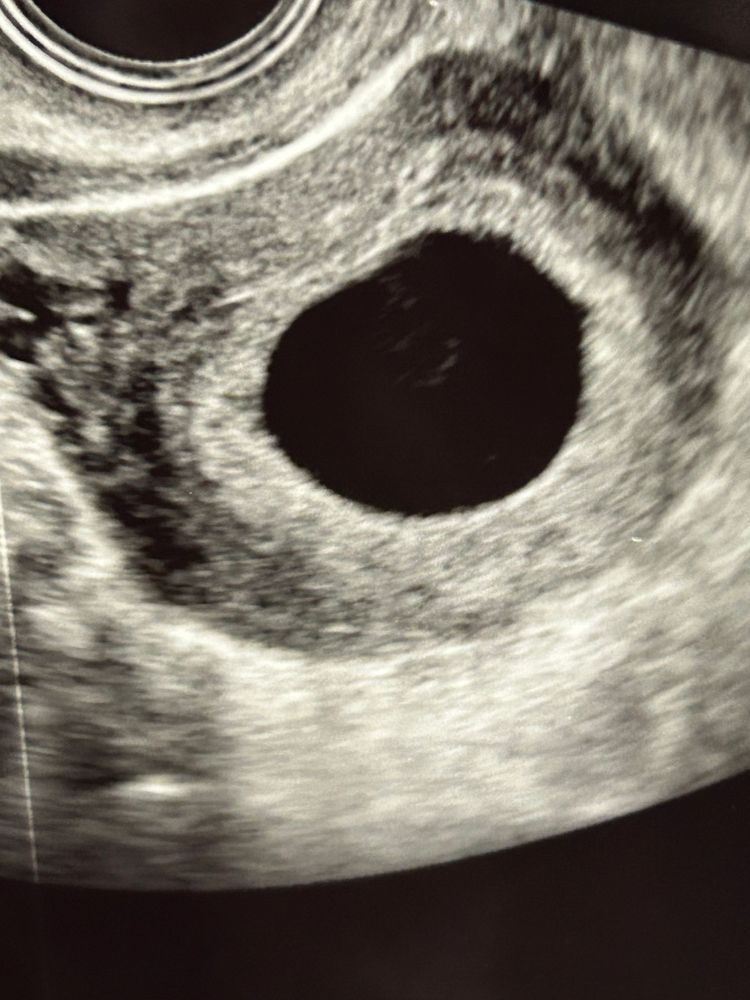

Что это в плодном яйце ?

К сожалению, но при таком размере ПЯ жм уже четко должен быть виден. На фото нет четкого изображения, это могут быть взвеси. Жм виден на узи начиная с 6мм плодного яйца, а эмбрион визуализируется, когда плодное яйцо становится больше 16-17мм. Я посмотрела свои узи на таком сроке. вот в 6н4д пя было 19мм и уже даже эмбрион с сердцебиением увидели.

На 1 фото очень похоже на жм

Где оно пустое. Вон "колечко внутри "- жм и формируется эмбрион. Почитайте 2 первые записи у меня в дневнике

Маргарита, мне ставили вчера срок 6 недель и анембрению , но я жду еще недельку - две и сделаю узи , узисты ничего не видят в плодном ( а домой приехала смотрю и на одном фото узи этот кружочек а на двух ниже уже не видно

Тата Савина, ну на этом фото прямо классика "кольцо с бриллиантом"

Увидела, что 21 мм. Повторите узи через 5 дней.

Размер ПЯ какой? Если больше 25 мм-Надежды нет. Это пустое плодное яйцо. А наличие взвеси и неоднородных включений еще больше свидетельствует в пользу НБ.

Ася, у меня 21 мм плодное яйцо

Пустое плодное яйцо 😞 К 6 неделям уже должен визуализироваться эмбриончик.